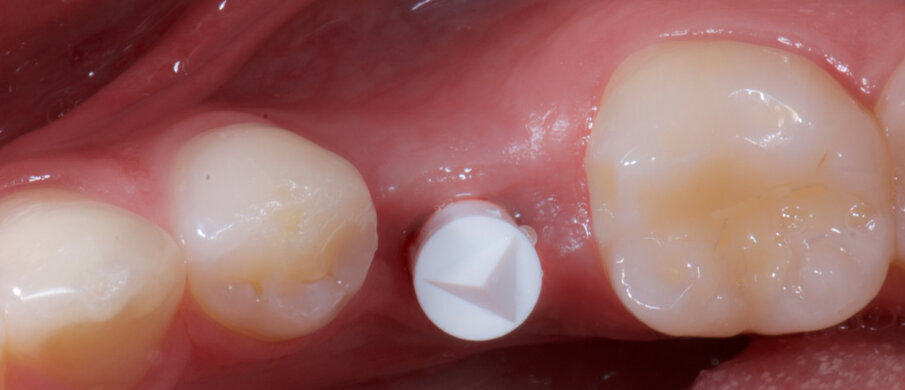

Fig. 5a_Gli scan body avvitati.

Fig. 5b_Gli scan body avvitati.